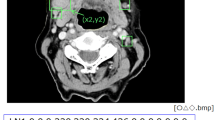

Seven-hundred and three CT images (178 with and 525 without extranodal extension) in 51 patients with cervical lymph node metastases from oral squamous cell carcinoma were enrolled in this study. CT images were cropped to an arbitrary size to include lymph nodes and surrounding tissues. All images were automatically divided into two datasets, assigning 80% as the training dataset and 20% as the testing dataset. The automated selection was repeated five times. Each training dataset was imported to a deep learning training system “DIGITS”. Five learning models were created after 300 epochs of the learning process using a neural network “AlexNet”. Each testing dataset was applied to each created learning model and resulting five performances were averaged as estimated diagnostic performances. A radiologist measured the minor axis and three radiologists evaluated central necrosis and irregular borders of each lymph node, and the diagnostic performances were obtained.